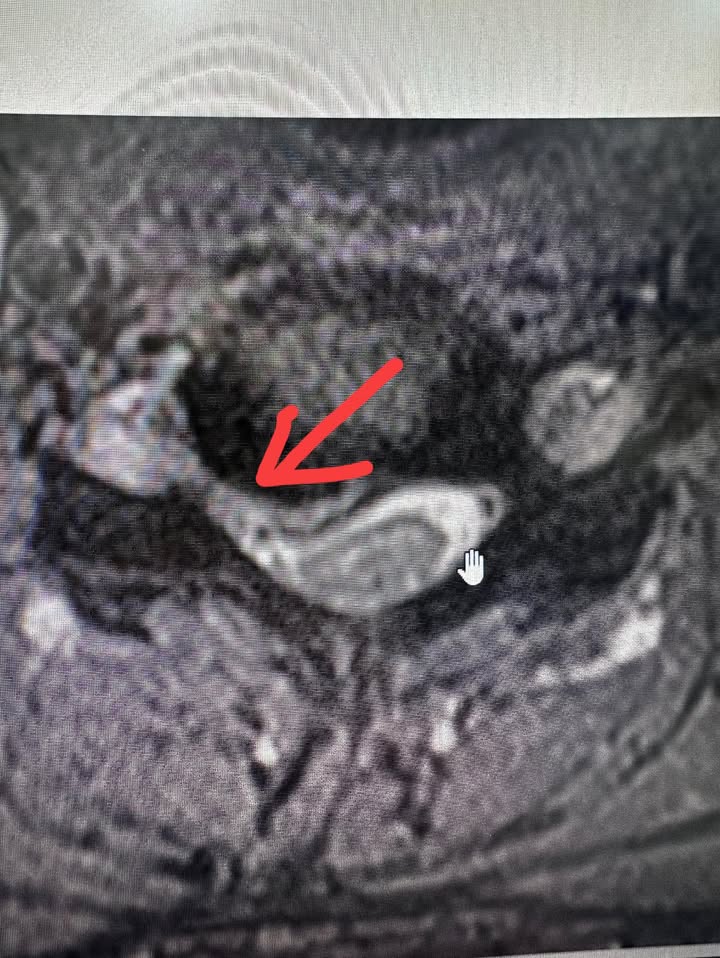

MRI的結果當天拍出來了!很明確——他的C5/C6頸椎神經根被壓迫,這是導致他疼痛和麻木的主要原因。我告訴他:「不需要開刀,我們可以用脊椎針刀微創療法試試。」他看著我,猶豫了一下,但還是點了點頭:「徐醫師麻煩你了,我信你。」